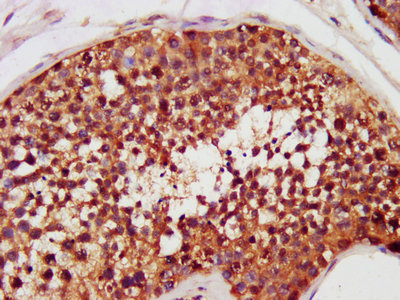

IHC image of CSB-PA005339LA01HU diluted at 1:200 and staining in paraffin-embedded human testis tissue performed on a Leica BondTM system. After dewaxing and hydration, antigen retrieval was mediated by high pressure in a citrate buffer (pH 6.0). Section was blocked with 10% normal goat serum 30min at RT. Then primary antibody (1% BSA) was incubated at 4°C overnight. The primary is detected by a biotinylated secondary antibody and visualized using an HRP conjugated SP system.